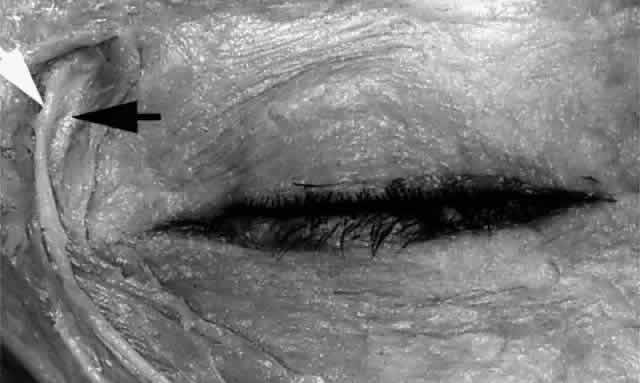

The canaliculus begins as the punctum, surrounded by a strong, fibrous ring known as the lacrimal papilla. The papilla and the included punctum, which has an average diameter of 0.2 to 0.3 mm, are located at the myocutaneous junction of the nasal aspect of the eyelid margin. The papilla (Fig. 18) is slightly elevated relative to the surrounding tissue and becomes more prominent with age because of atrophy of the encircling tissue.2,6

Fig. 18. The left lower papilla (arrow) is prominent in this elderly patient because of atrophy of the encircling tissue.

The lacrimal papilla, together with its punctum, is surrounded by pretarsal orbicularis muscle fibers that insert onto the posterior lacrimal crest and more posteriorly onto the periosteum of the medial orbital wall. Horizontal and posterior contraction of this muscle slightly inverts the medial eyelid margin to place the punctum in apposition with the lacrimal lake, allowing it to receive the tears.19